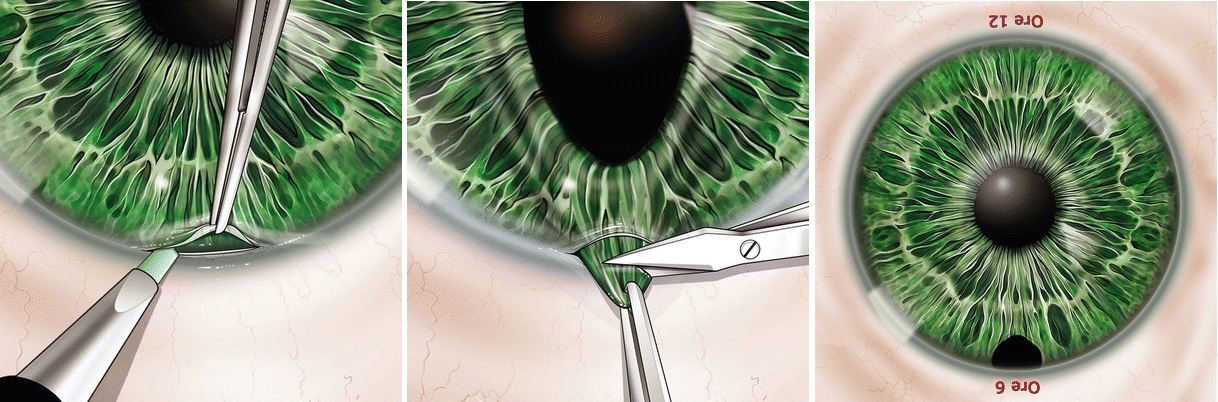

3. 수술적 홍채절제술 , Surgical iridectomy

환자가 세극등에 앉기 힘들거나, 협조가 안되는 경우,

각막혼탁이 있거나, 전방이 너무 얕아져서 레이저가 힘든경우에는

수술실에들어가서 주변부 각막에 절개를 가하고,

주변부 홍채를 잡아당겨, 일부를 절제해줍니다.

절제된 주변부 홍채를 통해서 방수가 빠져나가는 구멍을 만들어주면

안압이 떨어지면서, AACG attack 이 해결됩니다.